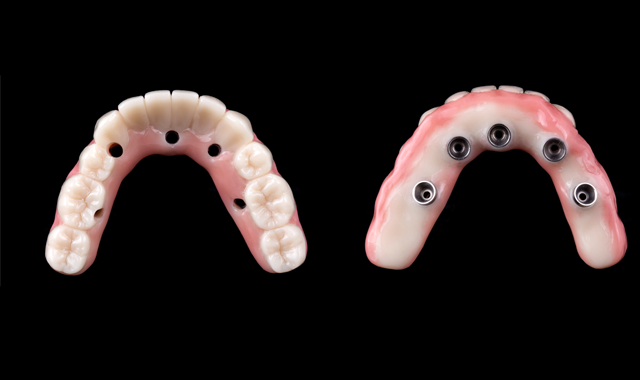

The final design of the zirconia prosthesis was done with monolithic zirconia for posterior teeth and only facial cut-back from canine to canine for porcelain veneering (Noritake CZR) and pink porcelain for the soft tissue area (GC Initial). A zirconia blank (Argen Z Esthetic 22 × 95 mm, Argen) was used for milling the definitive prosthesis (Figs. 12-13). The final zirconia restoration demonstrated excellent esthetic results (Figs. 14-15)

Fig. 12

Fig. 13